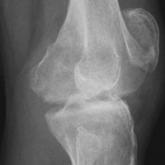

A Rare Case of Spontaneous Fusion of the Knee

To our knowledge, this article is the first report of a case of spontaneous and progressive bony fusion of a knee joint without a prior diagnosis...